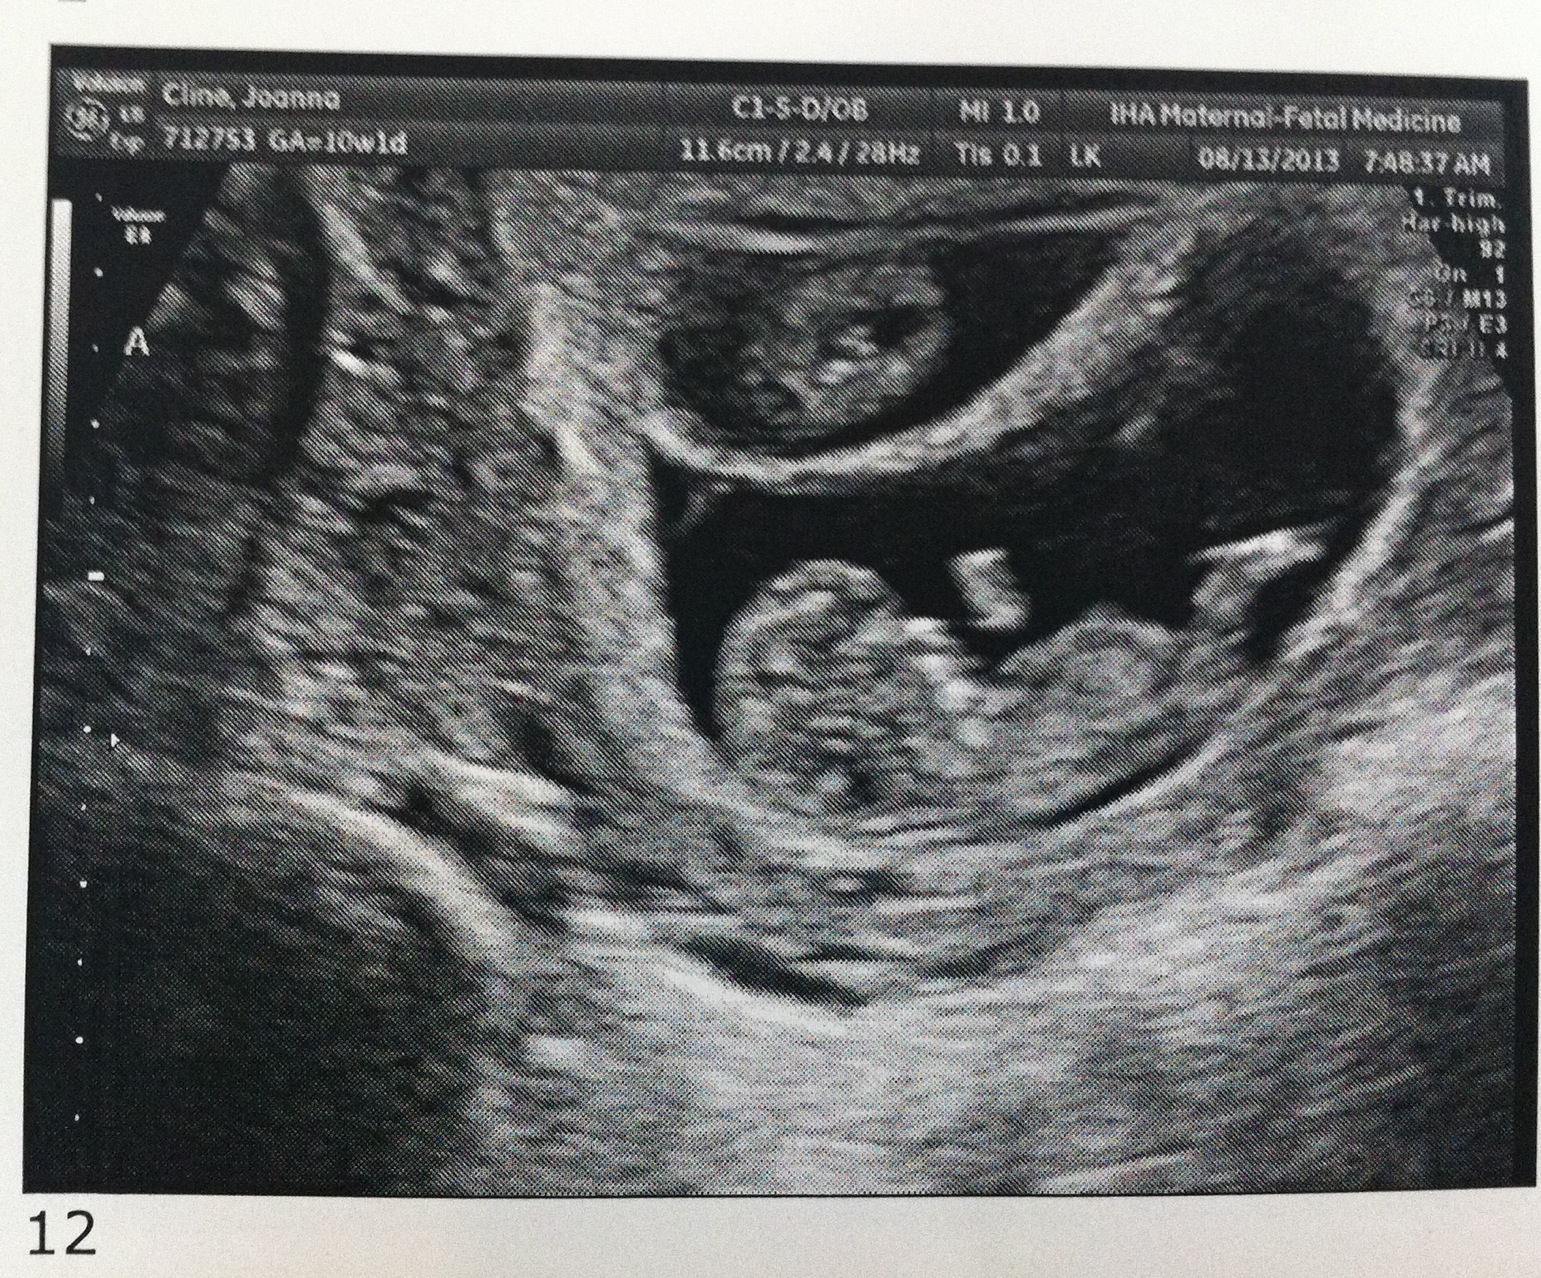

Good morning! I’m 10w1d today and we went for another ultrasound this morning. The u/s tech told us that everything looks exactly as she’d want it to at this point in the pregnancy. The heartbeats are great and they are wiggling around in there!

I’ve attached a few new photos – close ups of each and one group shot. 🙂